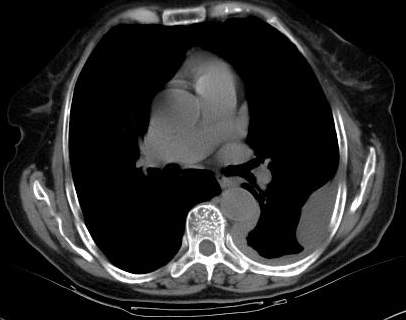

标题: CT0563:病历讨论,胸膜间皮瘤? [打印本页]

标题: CT0563:病历讨论,胸膜间皮瘤?

测ct值3-6hu,

既然ct值是3-6hu,还不如考虑包裹性积液。

从图片看,包裹性积液好象更合理,梭形,ct值3-5hu(在哪看到的?);胸膜间皮瘤如此规则,不多见。

左侧背部胸膜肥厚,伴包裹性积液,不考虑间皮瘤.

同意以上各位的高见,首先考虑包裹性积液,1.胸膜间皮瘤积液量一般较大,以游离性积液更为常见,2.可以看到增厚的胸膜结节